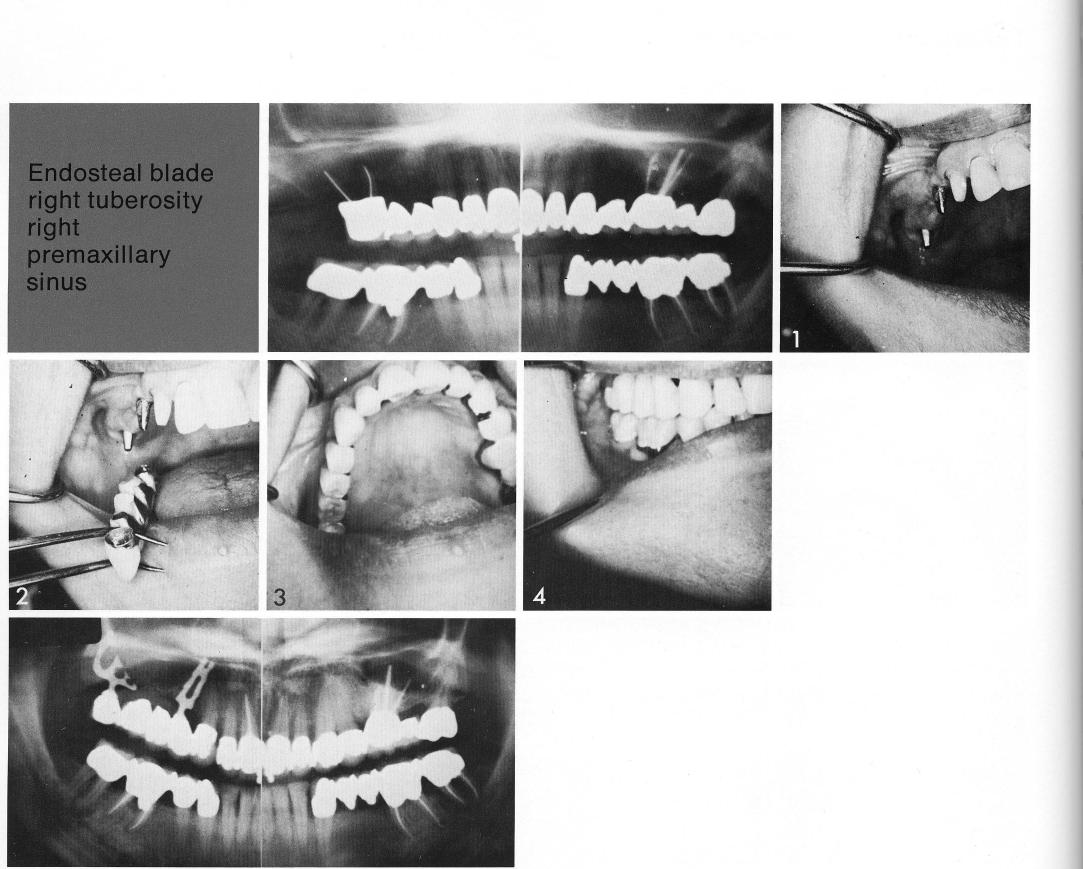

Two bladevents were used in a long, posteriorly edentulous span (1). The more proximal was a single-tooth bladevent set in front of the sinus, and the distal a tuberosity bladevent with a very low proximal shoulder (2). Such an implant can provide adequate support because its more distal shoulder is deep and set in solid tuberosity bone.

1 Two bladevent implants used in a long maxillary edentulous span